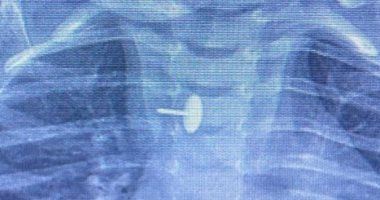

تمكن فريق جراحة الأطفال بمستشفى الأطفال التخصصي ببنها في محافظة القليوبية من إجراء عملية جراحية متقدمة لاستخراج دبوس ضغط من مريء طفلة تبلغ من العمر سنة وسبعة أشهر. كانت الطفلة قد ابتلعت الدبوس منذ ستة أشهر، مما شكل خطرًا على حياتها واستدعى التدخل الطبي الفوري.

أوضحت المستشفى أن الدبوس استقر داخل جدار المريء، مما أدى إلى صعوبة في البلع للطفلة طوال هذه المدة وعرّض حياتها للخطر. وتمت العملية باستخدام أجهزة حديثة مثل منظار الجهاز الهضمي وجهاز الأشعة “سي- آرم” ومنظار القصبة الهوائية، وضم فريق الجراحة الدكتور محمد متولي والدكتور وليد محمد والدكتور عبد الله أحمد والدكتور السيد الوصال.